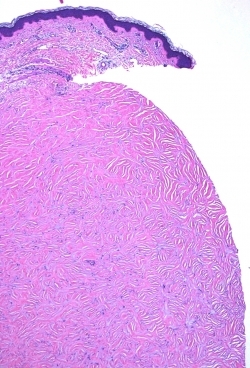

What is this neoplasm?

Sclerotic fibroma Sclerotic Fibroma (circumscribed storiform collagenoma): This can occur as an isolated lesion n the head or neck or upper extremities, but multiple lesions are associated with Cowden's disease which is an AD disorder linked to a mutation of PTEN on chromosome 10p. Histology: Dome shaped papule with an overlying attenuated epidermis. A well-circumscribed nodule composed of thickened homogenous collagen that is arranged in whorls with a thumbprint or grains of wood appearance is seen in the dermis. Overall the lesion exhibits low cellularity and the elastic fibers are absent. The tumor stains positively with vimentin, Factor XIIIA and focally for CD34.